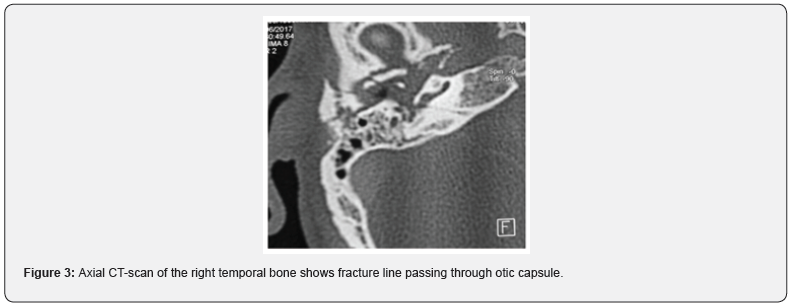

17% of patients presented Tinnitus. Facial paralysis in 43% cases. 32% due to transverse fracture, and 11% due to a longitudinal fracture. Determination of facial paralysis timing was based on the patient’s examination at admission, as well as the observations of the first responders in scene. The palsy was immediate in 28% and delayed in 15% (Table 1). 96% of cases presented a labyrinthine fracture (Figure 2,3), (on case of bilateral sever post traumatic sensorineural hearing loss had a normal CT scan in left temporal bone and a transversal right temporal bone fracture). Two cases of pneumolabyrinth: 8% (Figure 4). One case of bilateral fracture was noted: (Figure 5).